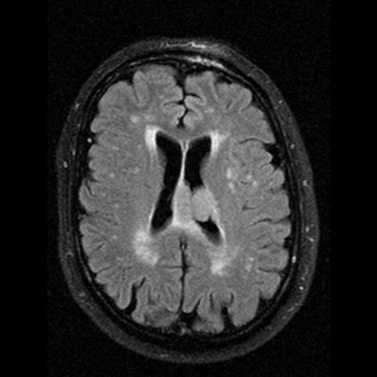

Image

1: Lacunar infarcts MRI, FLAIR.

Infarcts of microangiopathic origin can be lacunar infarcts that develop due to the complete or the partial occlusion of the cerebral arterioles. They predominantly occur at the basal ganglia, thalamus, internal capsule and the pons.

Biswanger’s disease (subcortical arteriosclerotic encephalopathy) is also results from microangiopathy.